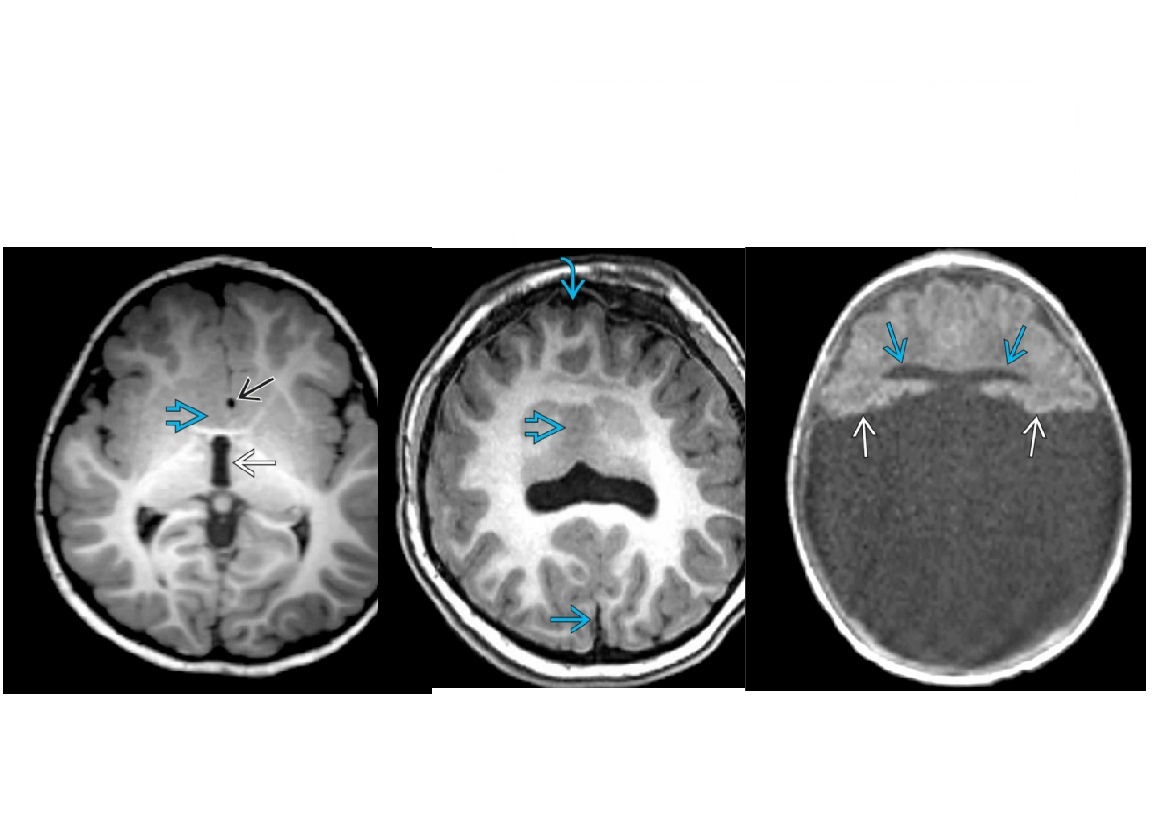

Child less than 1 = Neuroimaging interhemispheric SDH highest specificity for abuse of any intracranial injruy